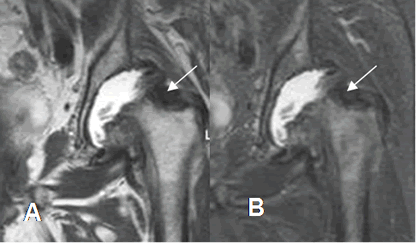

Fig 51. Sinovitis villonodular pigmentaria.

A: RM coronal en T2 y B: RM coronal en STIR. Derrame articular, con proliferación hipointensa de la sinovial, que rodean el cuello femoral. (Flechas).